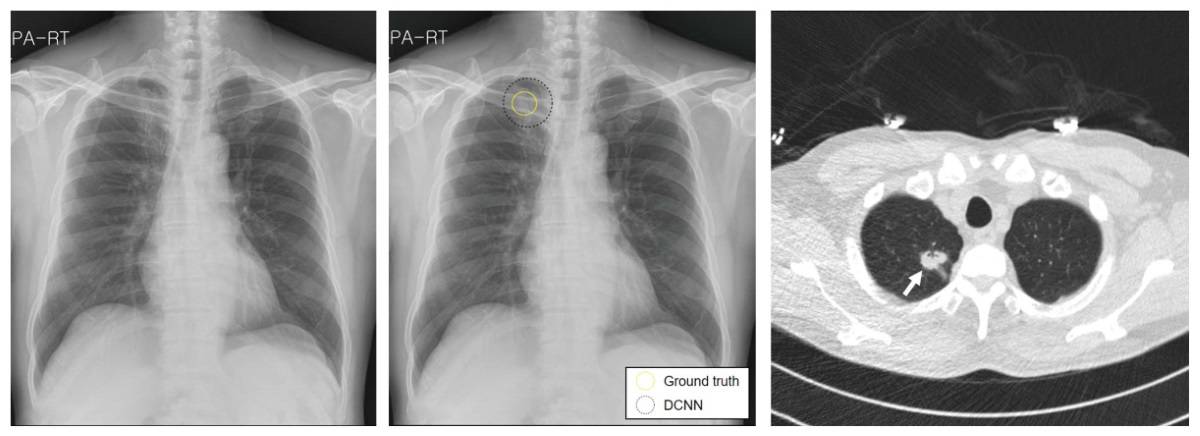

Lung Cancer Screening X Ray

Experience the clarity of Lung Cancer Screening X Ray with our curated collection of comprehensive galleries of images. featuring understated examples of photography, images, and pictures. designed to emphasize clarity and focus. Discover high-resolution Lung Cancer Screening X Ray images optimized for various applications. Suitable for various applications including web design, social media, personal projects, and digital content creation All Lung Cancer Screening X Ray images are available in high resolution with professional-grade quality, optimized for both digital and print applications, and include comprehensive metadata for easy organization and usage. Our Lung Cancer Screening X Ray gallery offers diverse visual resources to bring your ideas to life. Comprehensive tagging systems facilitate quick discovery of relevant Lung Cancer Screening X Ray content. Multiple resolution options ensure optimal performance across different platforms and applications. Time-saving browsing features help users locate ideal Lung Cancer Screening X Ray images quickly. The Lung Cancer Screening X Ray archive serves professionals, educators, and creatives across diverse industries. Instant download capabilities enable immediate access to chosen Lung Cancer Screening X Ray images. Whether for commercial projects or personal use, our Lung Cancer Screening X Ray collection delivers consistent excellence. Professional licensing options accommodate both commercial and educational usage requirements.